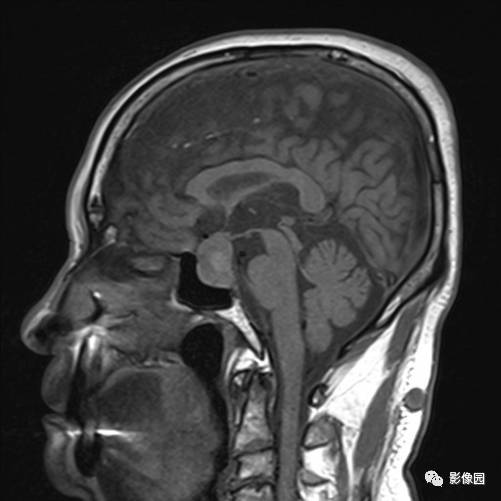

独孤求败:诊断为垂体瘤,蝶鞍扩大,鞍底下陷,鞍内见突向鞍上生长的团块状异常信号,T1WI呈等及稍高信号,T2WI呈等及低信号,增强扫描病灶呈明显不均匀强化;垂体柄显示不清,视交叉受压上抬。

bnzhang07:这是典型的垂体大腺瘤,垂体大腺瘤冠状扫描显示肿瘤呈哑铃状或“束腰征”,这是由于肿瘤伸于鞍上,中部受鞍隔束缚的原因。

lovethemoon:这不是颅咽管瘤,而是垂体瘤,颅咽管瘤时可见正常的垂体结构,此患者看不到正常的垂体结构,病变内短T1短T2异常信号是出血,垂体瘤合并了出血,颅咽管瘤囊变时的信号一般是长T1长T2。